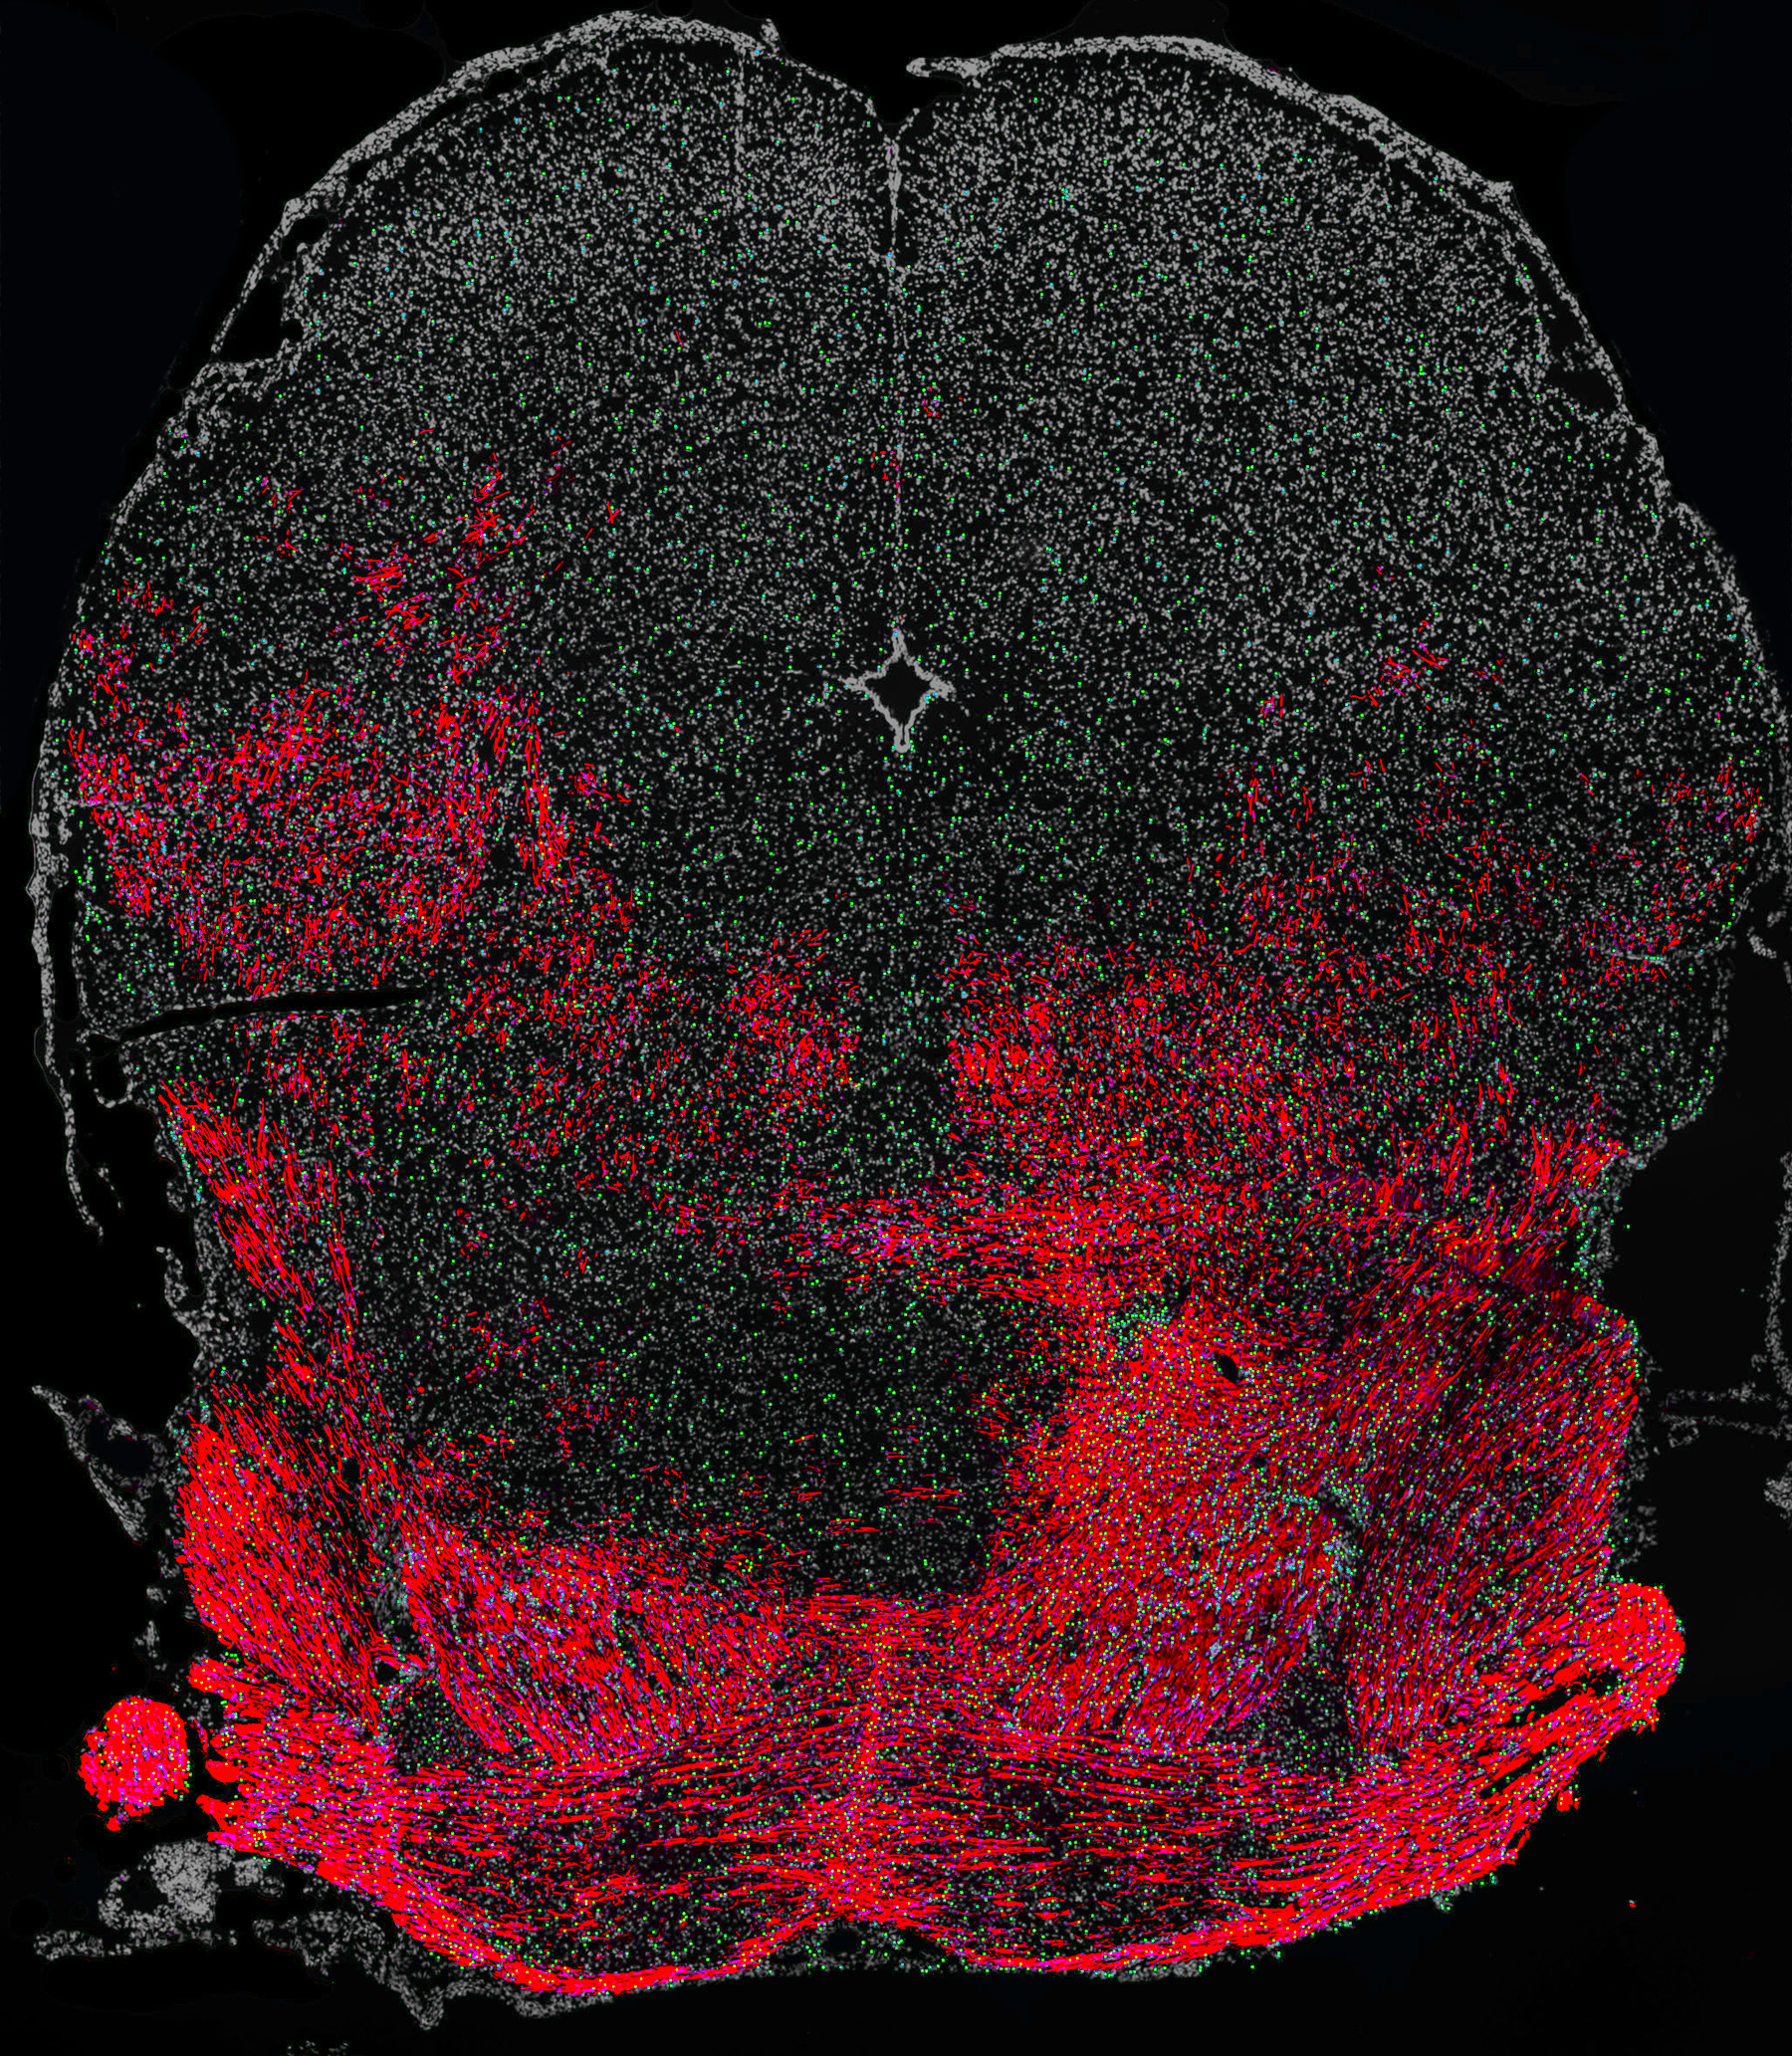

The brainstem of a myelin-deficient mouse that received a transplant of human OPCs a few days after birth and was then treated with the drug solifenacin. Daily treatment enhanced the capacity of human cells (labeled in green) to produce myelin (shown in red), which led to improved hearing in the mouse.

To test whether the drug could boost myelin synthesis, the researchers transplanted human oligodendrocyte progenitor cells into mice that could not make myelin. The result was increased differentiation and myelin synthesis from the transplanted human cells.